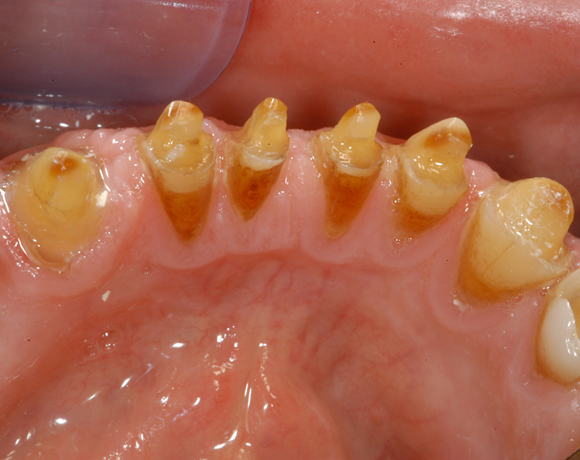

Im vorliegenden Patientenfall waren die Zähne 11 – 26 mit einer provisorischen Brücke versorgt, der Patient konnte damit aber nicht essen. Auch im Unterkiefer waren die vorhandenen Kronen und Brücken insuffizient. Es wurde eine komplette Neuversorgung für Ober- wie Unterkiefer geplant.